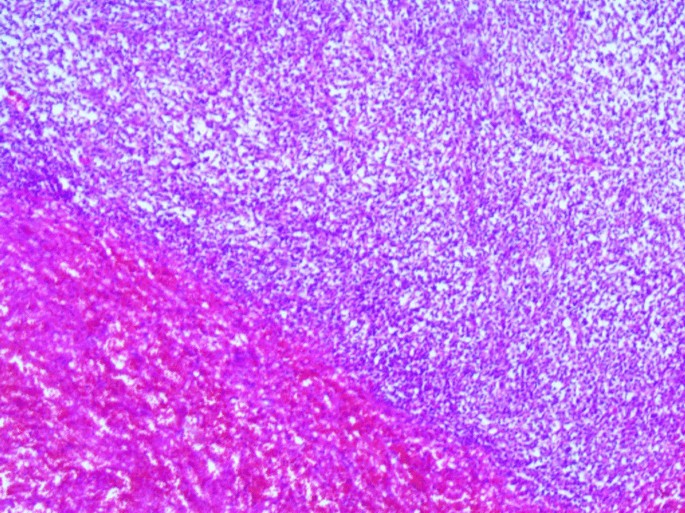

View Diffuse Large B Cell Lymphoma Spleen UK. Obesity is a risk factor. May arise from follicular lymphoma.

Involvement of splenic hilar lymph nodes and bone marrow (usually focal) can occur in primary dlbcl.

B cell nhl's include burkitt lymphoma, diffuse large b cell lymphoma, mantle cell lymphoma, and marginal zone lymphoma. Obesity is a risk factor. Our understanding of this heterogeneity has increased with the development of several molecular technologies, resulting in the identification of genetic subtypes and important biologic. A united kingdom national cancer research institute trial.